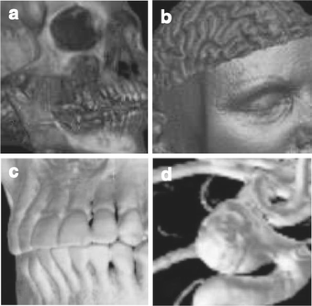

Fig 3.

Fig 4.